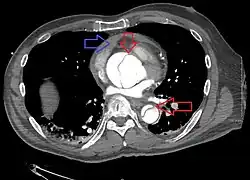

-

Aortic dissection -

CT with contrast demonstrating aneurysmal dilation and a dissection of the ascending aorta (type A Stanford) -

Chest CT with descending (type B Stanford) aortic dissection (red circle)

Type A dissection with pericardial effusion as a result.